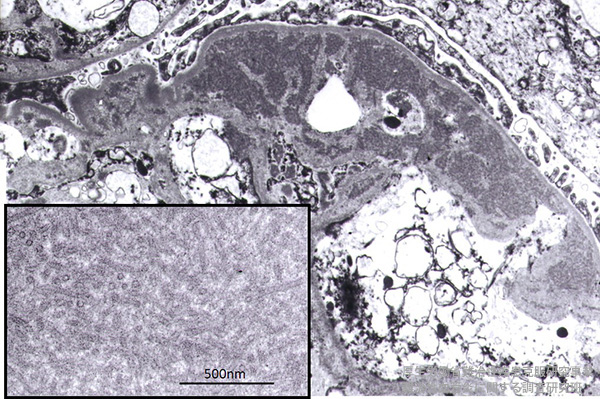

腎組織の電顕検索では、内皮下に高電子密度沈着物を認める。

沈着物は、50000倍程度に強拡大すると、特徴的な沈着物のシリンダー状の構造が認められた(挿入図)。